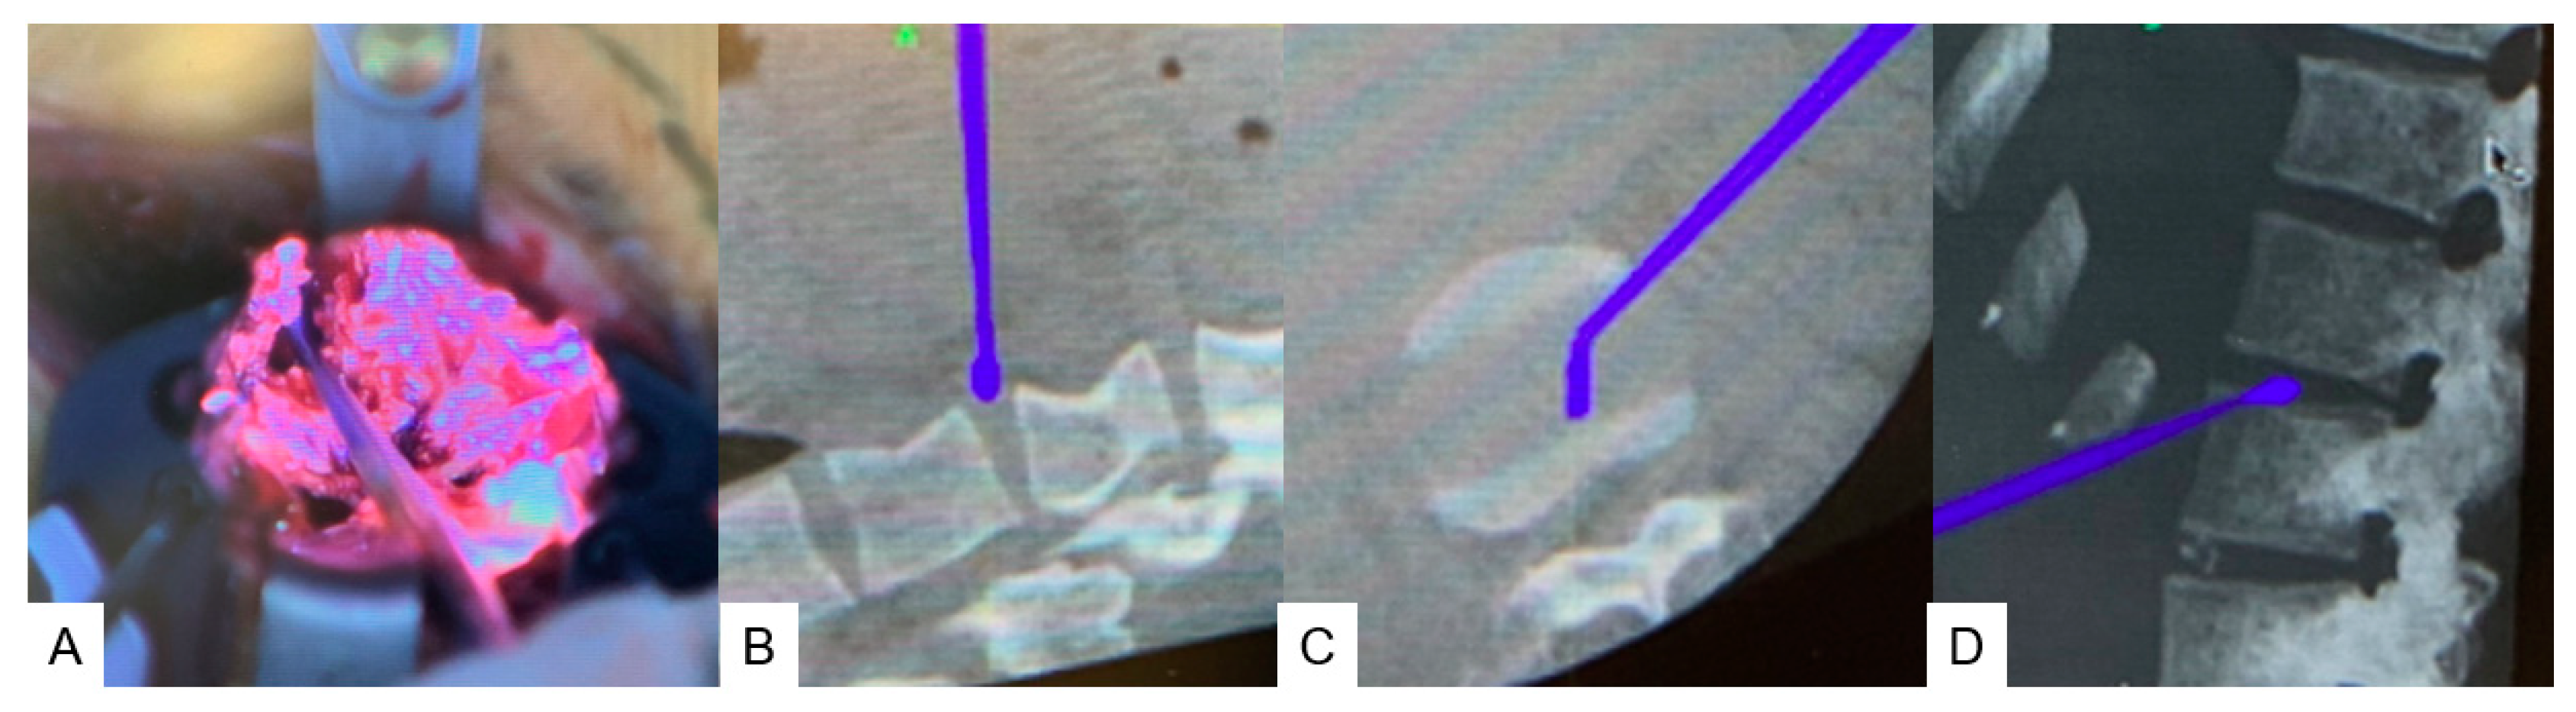

2.4.1. Anterior Discectomy

2.4.2. Posterior Osteotomy